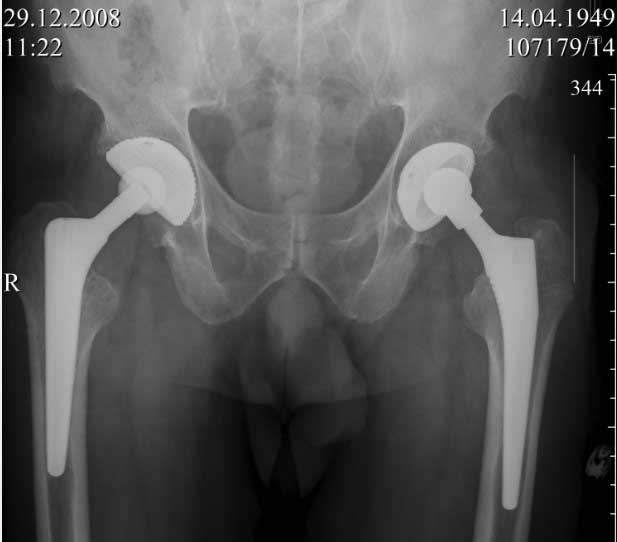

Пациент 60 лет, мужчина. Оперирован в 2007 году, поочередно оперированы два тазобедренных сустава с интервалом в 4 месяца. В 2008 году оперирован на сердце(аорто-коронарное шунтирование).Операция осложнилась инфицированием операционной раны в области грудины, лечился в гнойном отделении.

В конце 2008 года отметил боли в правой паховой области при опоре на правую ногу. На рентген снимках таза с тазобедренными суставами явных признаков нестабильности вертлужного компонента не обнаружено. В 2009 году нейрохирурги его "успешно" прооперировали на L\3-\4 связывая болевой синдром в правой паховой области с наличием грыжи указанного межпозвонкового диска. Состояние только ухудшилось, больной уже не мог долго сидеть, боль прогрессировала . Его в 2009 и 2010 годах смотрел ортопед, делались рентгенснимки, но почему то приходили к выводу что эндопротез справа стабилен. В марте 2011 года я впервые увидел его, через одну неделю после этого был прооперирован. На операции вертлужный компонент при упоре на него инструментом прокручивался во впадине и без труда был извлечен.

Эндопротез Ножка Cerafit компании Ceraver- чашка той же компании.

ниже снимок в 2008 году

далее снимок в 2009 году

далее снимок у меня на приеме